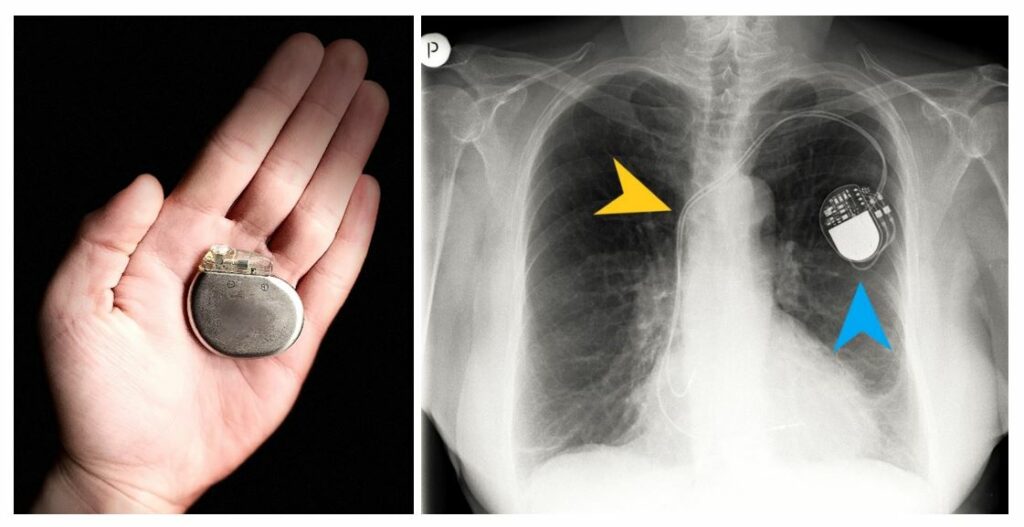

„Centrala” ta (zwana „puszką”) w zależności od producenta i typu urządzenia (jedno- lub dwujamowe) może mieć różne kształty i rozmiary, jednak zwykle przypomina metalowy dysk o średnicy ok. 4 cm. Zawiera baterię (wystarczającą średnio na ok. 8 lat) oraz układ elektroniczny, który analizuje aktywność serca zbadaną za pośrednictwem elektrod i w razie potrzeby wysyła stymulujące impulsy. Działa więc jak metronom, wybijający tempo, kiedy serce samo zgubi rytm. Puszka rozrusznika umieszczana jest nie poza ciałem (jak w przypadku stymulacji czasowej), ale zaszywana pod skórą lub pod mięśniami, zwykle poniżej lewego obojczyka. Miejsce, w którym zaszywane jest urządzenie, nazywa się „lożą”. Po przyłożeniu do skóry nad lożą specjalnego urządzenia (tzw. „programatora”), lekarz jest w stanie zmienić ustawienia stymulatora, dostosowując je do aktualnego stanu pacjenta.

Ryc. 1 i 2: Puszka stymulatora na dłoni autora. W tym małym urządzeniu znajduje się bateria, działająca nawet kilkanaście lat! Obok zdjęcie rentgenowskie klatki piersiowej pacjenta ze stymulatorem dwujamowym – widoczna puszka stymulatora (niebieski grot) i elektrody umieszczone w układzie żylnym (żółty grot).